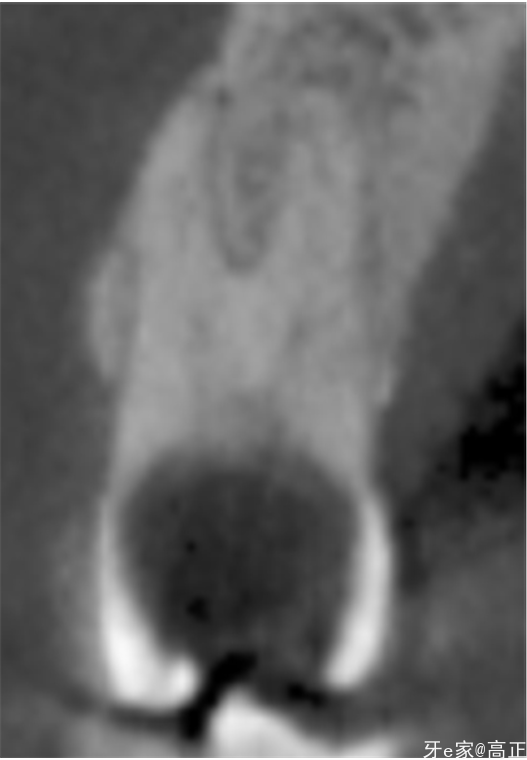

辅助检查:龋坏穿髓,余无异常

X片检查